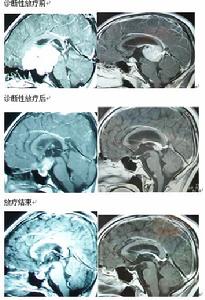

實驗性放療(Radiation tests)又稱診斷性放療(Diagnostic radiotherapy)是在根據臨床表現、影像學、腫瘤標記物等高度懷疑生殖細胞瘤時,在沒有病理診斷的情況下採用小劑量的放療,根據腫

生殖細胞瘤的高發地日本於1983年首先提出實驗性放療的概念,並運用至今。專家提醒:要確認腫瘤或占位的病理性質只有手術切除或者活檢兩種方法.試驗性放療是間接判斷生殖細胞腫瘤(GCTs)/占位具體性質的一種簡便.實用,較安全的方法,多數情況下可區分germinoma和NG-GCTs或其它性質占位,但通過此方法得出的初步診斷,是個人的主觀判斷,只有經過長期實踐,積累了豐富臨床經驗的醫生才能勝任,才能最大限度的減少誤診誤治的可能.見圖。

臨床疑NG-MGCTs且AFP陽性患者可採用PEB,VIP等方案,化療目的:判斷腫瘤對化療的敏感性,決定下一步治療方案。見圖。松果體區生殖細胞瘤